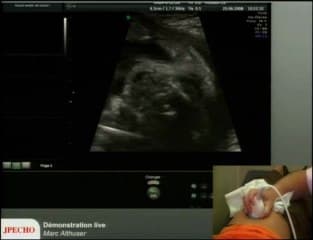

La plus grande ressource vidéo en échographie fœtale de France. Conférences, cours magistraux, démonstrations pratiques et podcasts par les experts du Collège Français d'Échographie Fœtale.

Vous y trouverez des conférences présentées lors des congrès nationaux et internationaux, des cours magistraux dispensés par des experts reconnus, des démonstrations pratiques sur des cas cliniques réels, ainsi que des podcasts et tables rondes sur les dernières avancées de la spécialité.